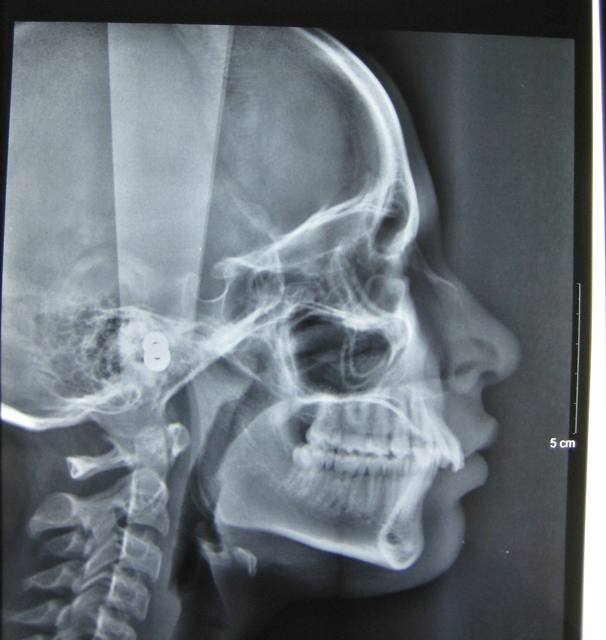

J'ai une patiente de 14 ans qui présente une full classe II due à un maxillaire en proposition car sur une base du crâne trop longue en antérieur. Le maxillaire a une longueur normale.

Voici les photos, radios et moulages du cas

Le maxillaire n'est pas si avancé que cela, par rapport a mac namara ( mais c'est normale, si c'est la base du crane qui est augmenté ) : donc : chirurgie pour raccourcir la base du crane ?

Sinon, extraction 14 24, c'est quand même moins lourd qu'un Lefort.